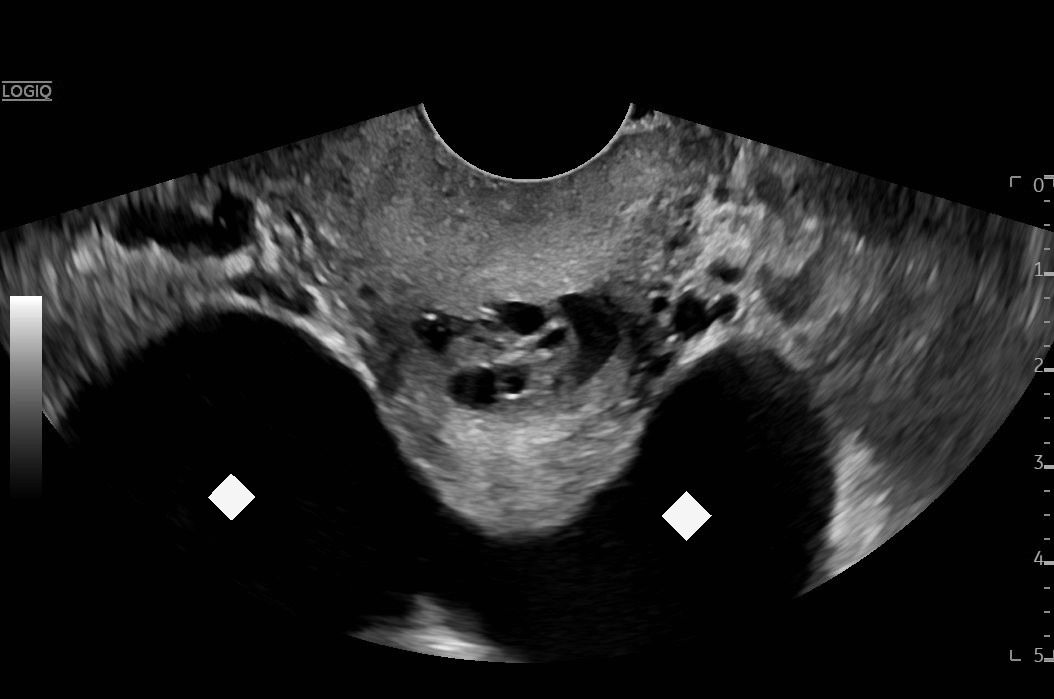

Ovarian hyperstimulation syndrome (OHSS) is a potentially life-threatening complication of assisted reproductive technology (ART). Here, we present the case report of a 30-year-old female undergoing infertility treatment who presented to the emergency department (ED) with nausea and vomiting, abdominal distention, and shortness of breath. On physical exam, she had notable ascites. Computed tomography (CT) of the abdomen and pelvis and pelvic ultrasound (US) revealed significant ascites and enlarged ovaries with multiple cysts. She was diagnosed with severe OHSS and admitted to obstetrics and gynecology (OBGYN) service for five days where she underwent intravenous (IV) hydration and paracentesis. This case report reviews the clinical presentation, categorization, management, and prevention of OHSS and provides examples of imaging findings consistent with the condition.